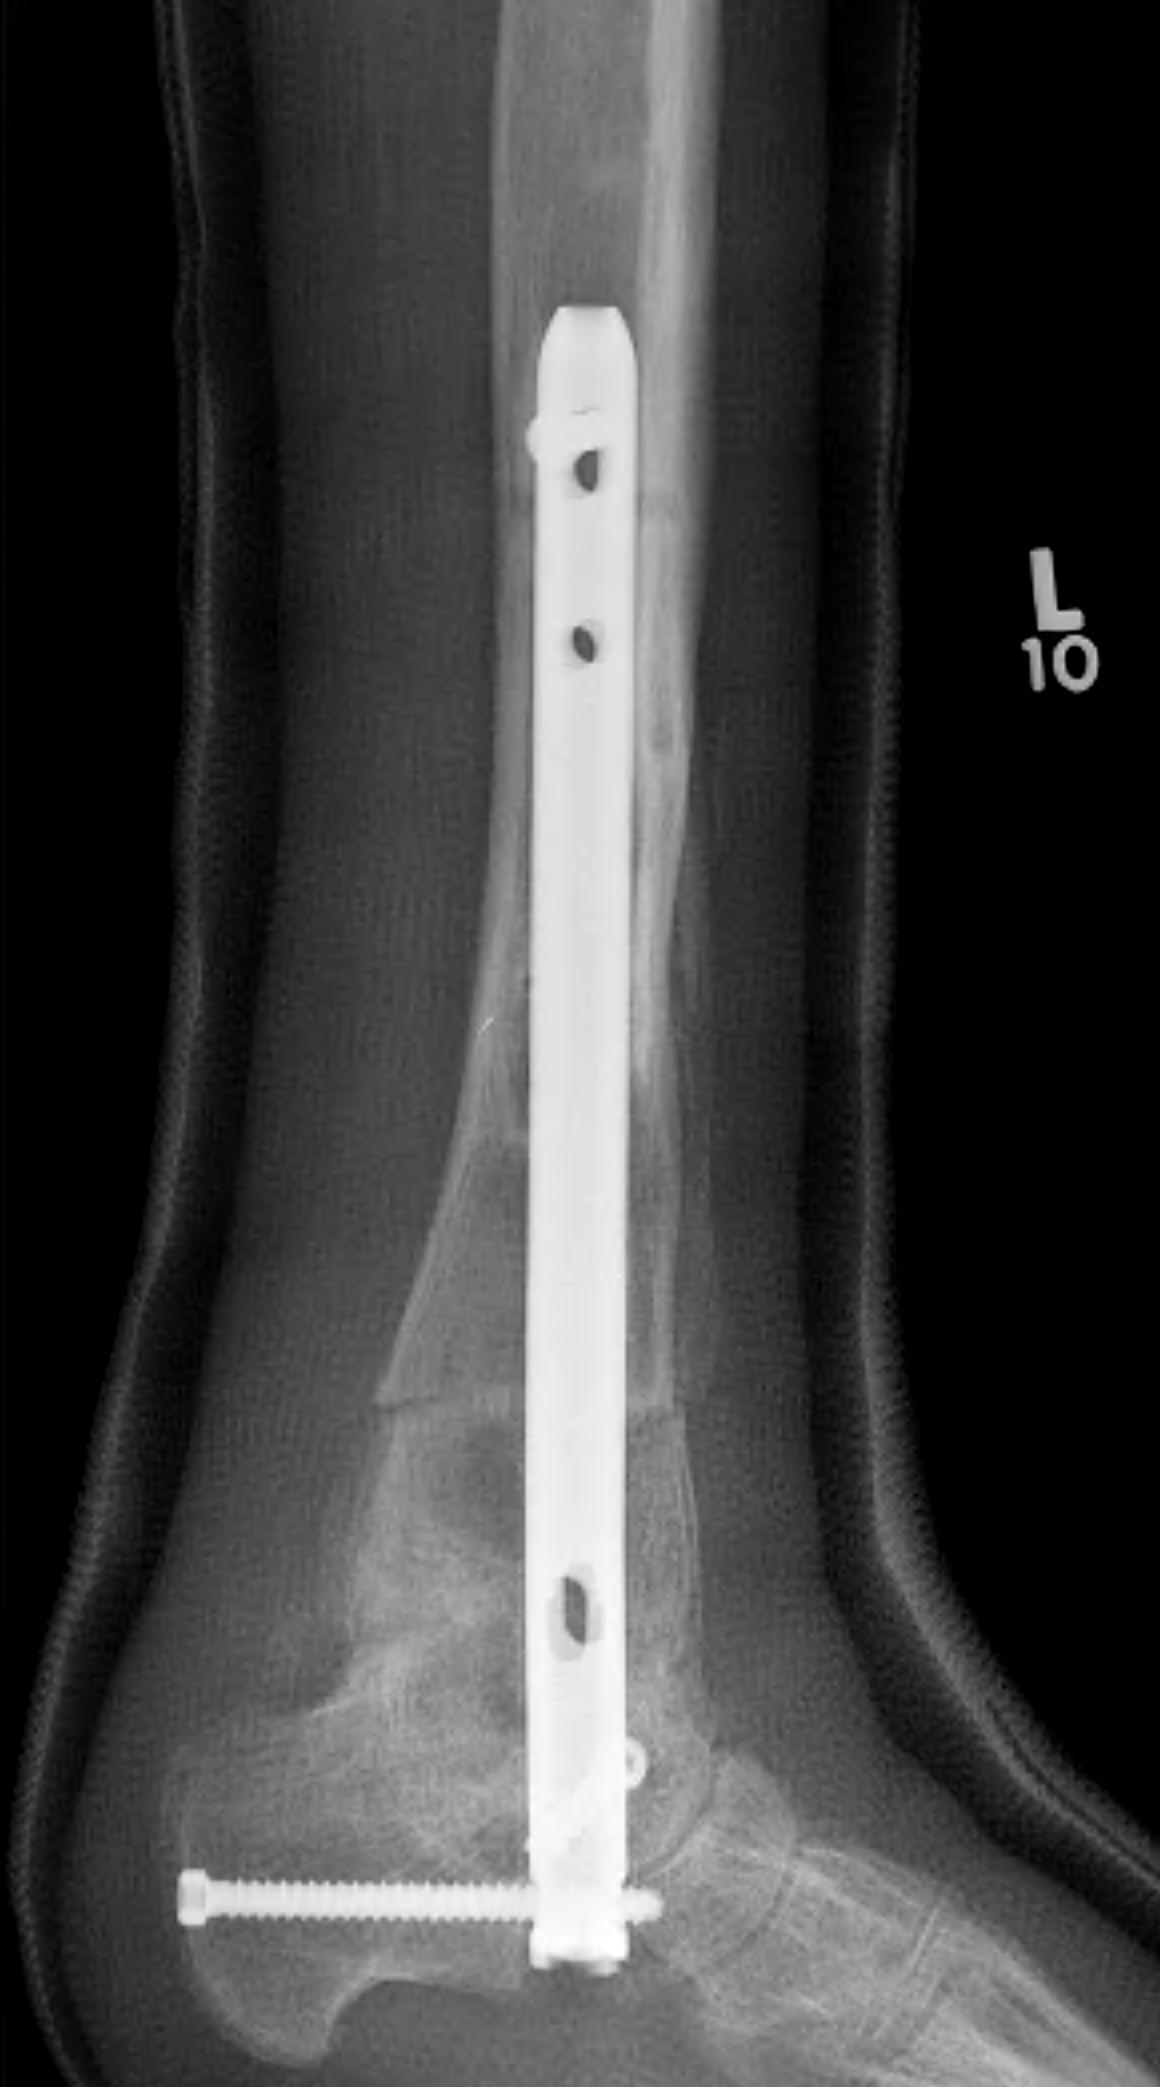

Tibiotalocalcaneal (TTC) / hindfoot nail

Insertion point

- in line with 2nd metatarsal / center of heel pad

- junction of posterior 2/3 and anterior 1/3 heel

- should pass through anterior aspect posterior subtalar joint

- posterior to lateral plantar artery and nerve

Screw fixation

- distal screw fixation in calcaneum +/- talus with jig

- compression

- proximal screws medial to lateral